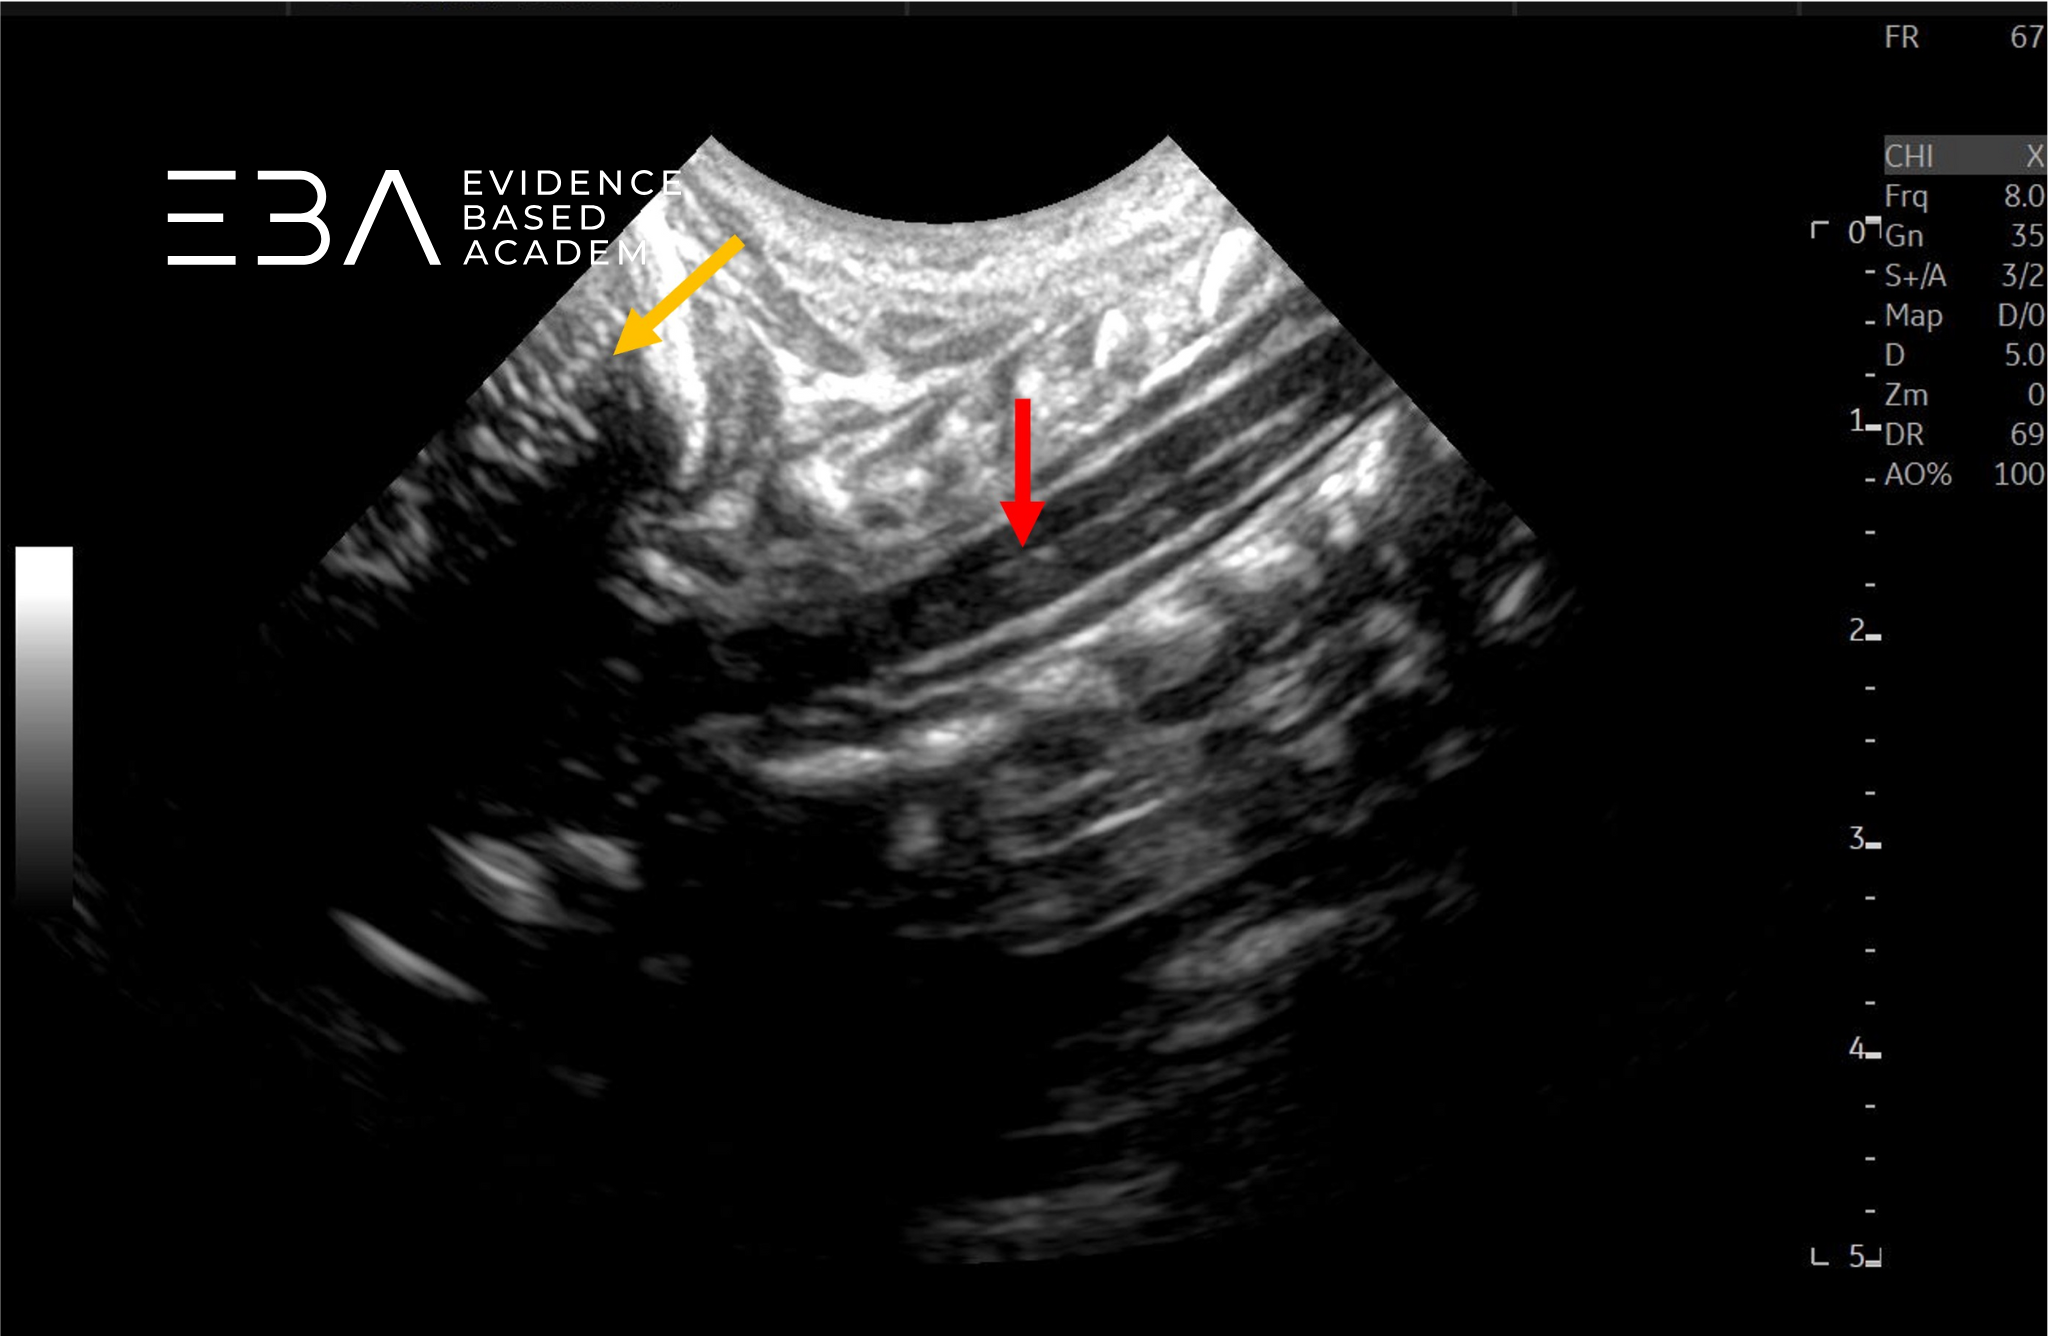

fot. 2

Przekrój podłużny kanału kręgowego w odcinku szyjnym, głowica mikrokonweksowa. Czerwoną strzałą zaznaczono rdzeń kręgowy, pomarańczową strzałą móżdżek.

fot. 3

Przekrój podłużny kanału kręgowego w odcinku szyjnym, głowica mikrokonweksowa. Czerwoną strzałą zaznaczono otwór wielki, pomarańczową strzałą móżdżek.